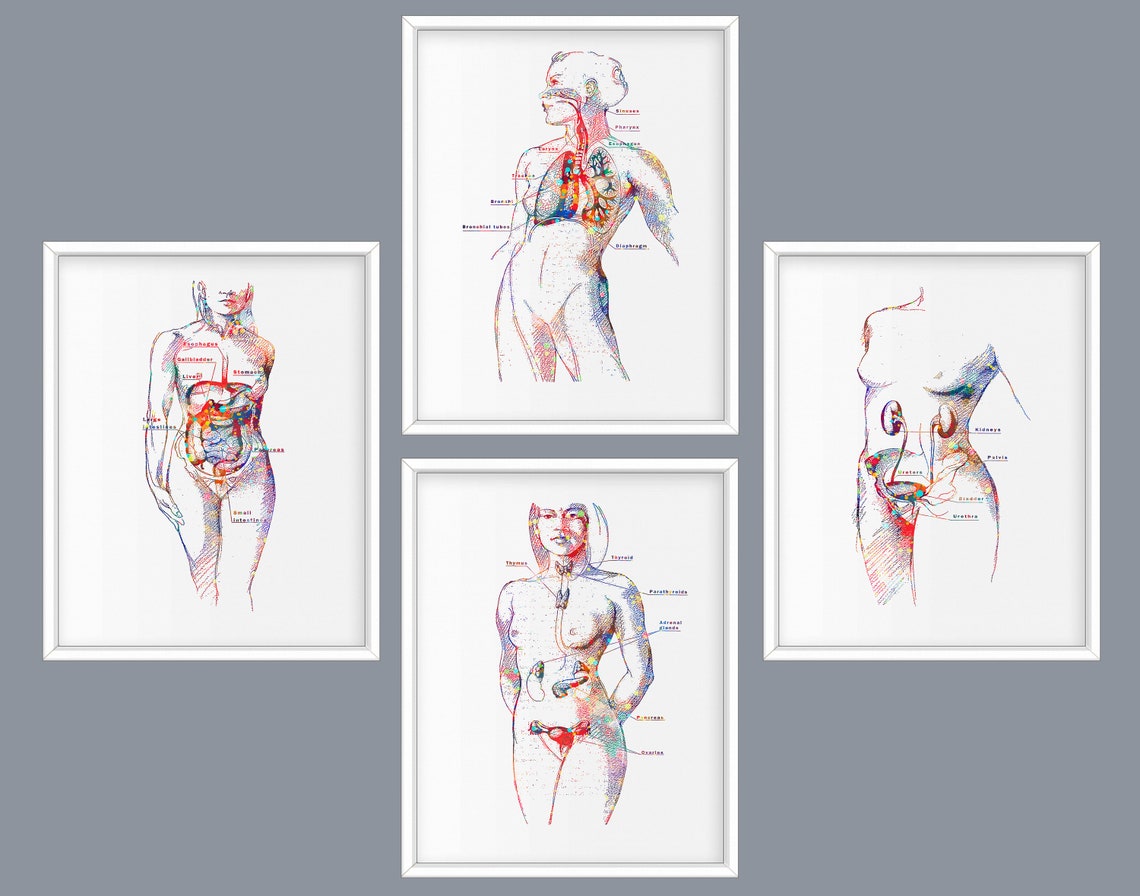

www.alamy.com5 Female Anatomy Art Woman Physiology Art Medical Artwork - Etsy

www.alamy.com5 Female Anatomy Art Woman Physiology Art Medical Artwork - Etsy

fineartamerica.comFemale Anatomy Art Print Women Body Torso Drawing Illustration Modern

fineartamerica.comFemale Anatomy Art Print Women Body Torso Drawing Illustration Modern